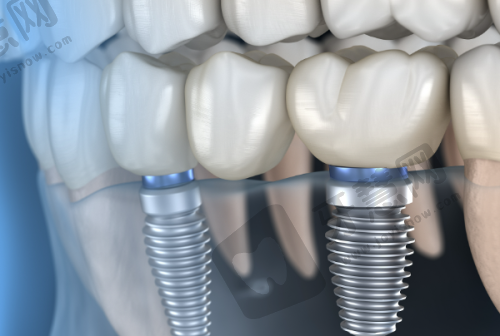

丰富的诊疗经验:艾军 医生作为北京西诺口腔(常营店)的主治医师,拥有长达36年的牙科诊疗经验。他曾在三等甲国有医院口腔科任职30余年,积累了丰富的口腔治疗技能。专精领域专长:艾军 医生在多个专精领域表现出色,尤其擅长种植牙、根管治疗以及儿童全口涂氟等项目。他技术娴熟、操作规范,能够有效实施微痛治疗,让患者在舒适的状态下完成治疗。凭借不错的医术和良好的医德,艾军 医生深受患者的信任和赞誉,在种植领域以及口腔美容修复领域有着丰富的临床经验。

种植牙手术费用:艾军 医生开展的种植牙手术费用一般在5000 - 30000元不等,这取决于种植体的品牌、种植的难度等。如果选择较为有名的进口种植体,费用会相对较高;而一些国产种植体价格则较为亲民。根管治疗费用:根管治疗的费用通常在500 - 2000元左右,根据牙齿的部位和根管的复杂程度有所波动。儿童全口涂氟费用:儿童全口涂氟的费用相对较低,大概在100 - 300元。北京西诺口腔(常营店)会根据患者的具体情况制定个性化的治疗方案,并明确告知费用详情。

有患者分享,之前找艾军 医生做了种植牙手术,整个过程体验非常好。手术前,艾军 医生详细地给患者讲解了手术流程和注意事项,让患者心里有了底。手术中,他操作十分娴熟,而且真的实现了微痛治疗,患者几乎没有感觉到明显的疼痛。术后,医生还耐心地告诉患者护理方法。在修复过程中,患者按照医生的嘱咐进行护理,伤口愈合得特别快,也没有出现什么不适症状。现在患者的种植牙使用起来和真牙一样,非常感谢艾军 医生,他的医术和服务都让患者十分满意。